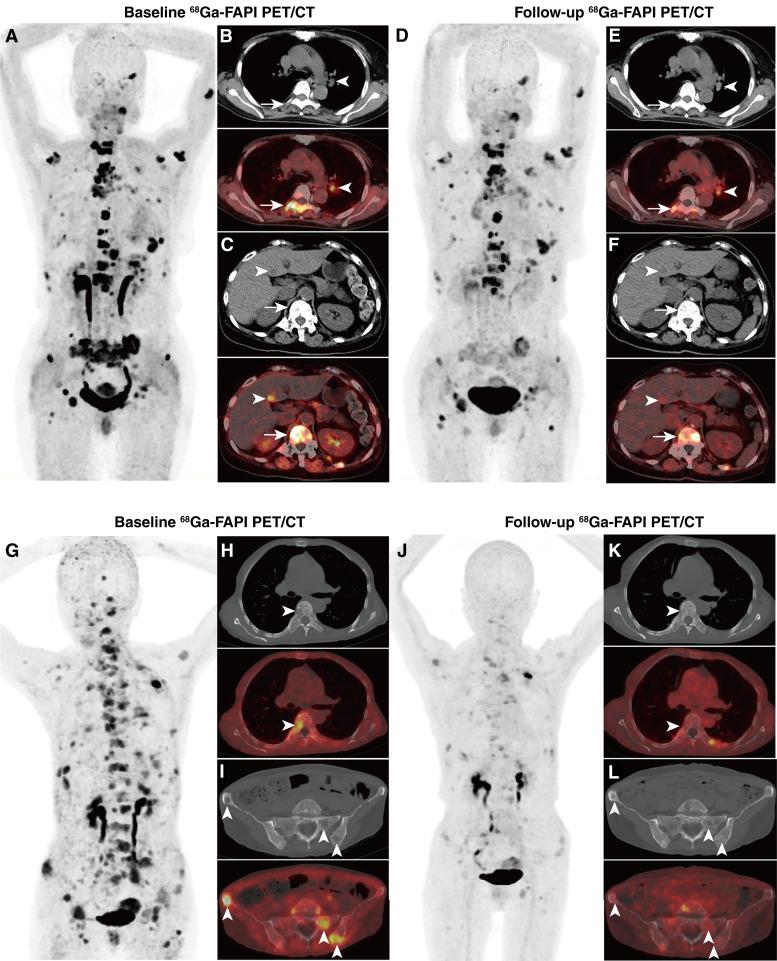

Fibroblast activation protein (FAP) is highly expressed in cancer-associated fibroblasts and certain tumor cells, making it a promising therapeutic target for various malignancies. This study evaluated the efficacy and safety of 177Lu-Evans blue-FAP inhibitor (177Lu-LNC1004) radioligand therapy (RLT) for treating end-stage metastatic tumors.

This single-arm, single-center, phase II trial included 28 patients with progressive metastatic malignancies (11 types) and high FAP expression (defined as a maximum standardized uptake value ≥10 in >50% of tumors) who had exhausted all approved therapies, screened between June 2022 and April 2024. Patients were scheduled to receive four 177Lu-LNC1004 RLT cycles at 3.33 GBq/cycle every 6 weeks. The primary endpoint was post-RLT radiologic response. The secondary endpoints were progression-free survival (PFS), overall survival (OS), dosimetry, and safety.

Eastern Cooperative Oncology Group scores >2 were observed in 68% of patients. Overall, 63 177Lu-LNC1004 RLT cycles were performed, with 19 (68%) patients undergoing ≥2 cycles. Disease control was achieved in 13 (13/28, 46%) patients, with 4 and 9 patients demonstrating partial response and stable disease, respectively, and associated with improved PFS and OS (P < 0.001). The mean absorbed dose in tumors was 4.69 ± 3.83 Gy/GBq (1.18-25.03 Gy/GBq). Treatment-related grade 3/4 hematotoxicity was observed in six (21%) patients, with thrombocytopenia, leukopenia, and neutropenia most prevalent. No grade 3/4 hepatotoxicity or nephrotoxicity was observed.

FAP-directed RLT using 177Lu-LNC1004 at 3.33 GBq/cycle was well tolerated with an acceptable toxicity profile. Nearly half of patients achieved disease control, which was associated with prolonged PFS and OS.